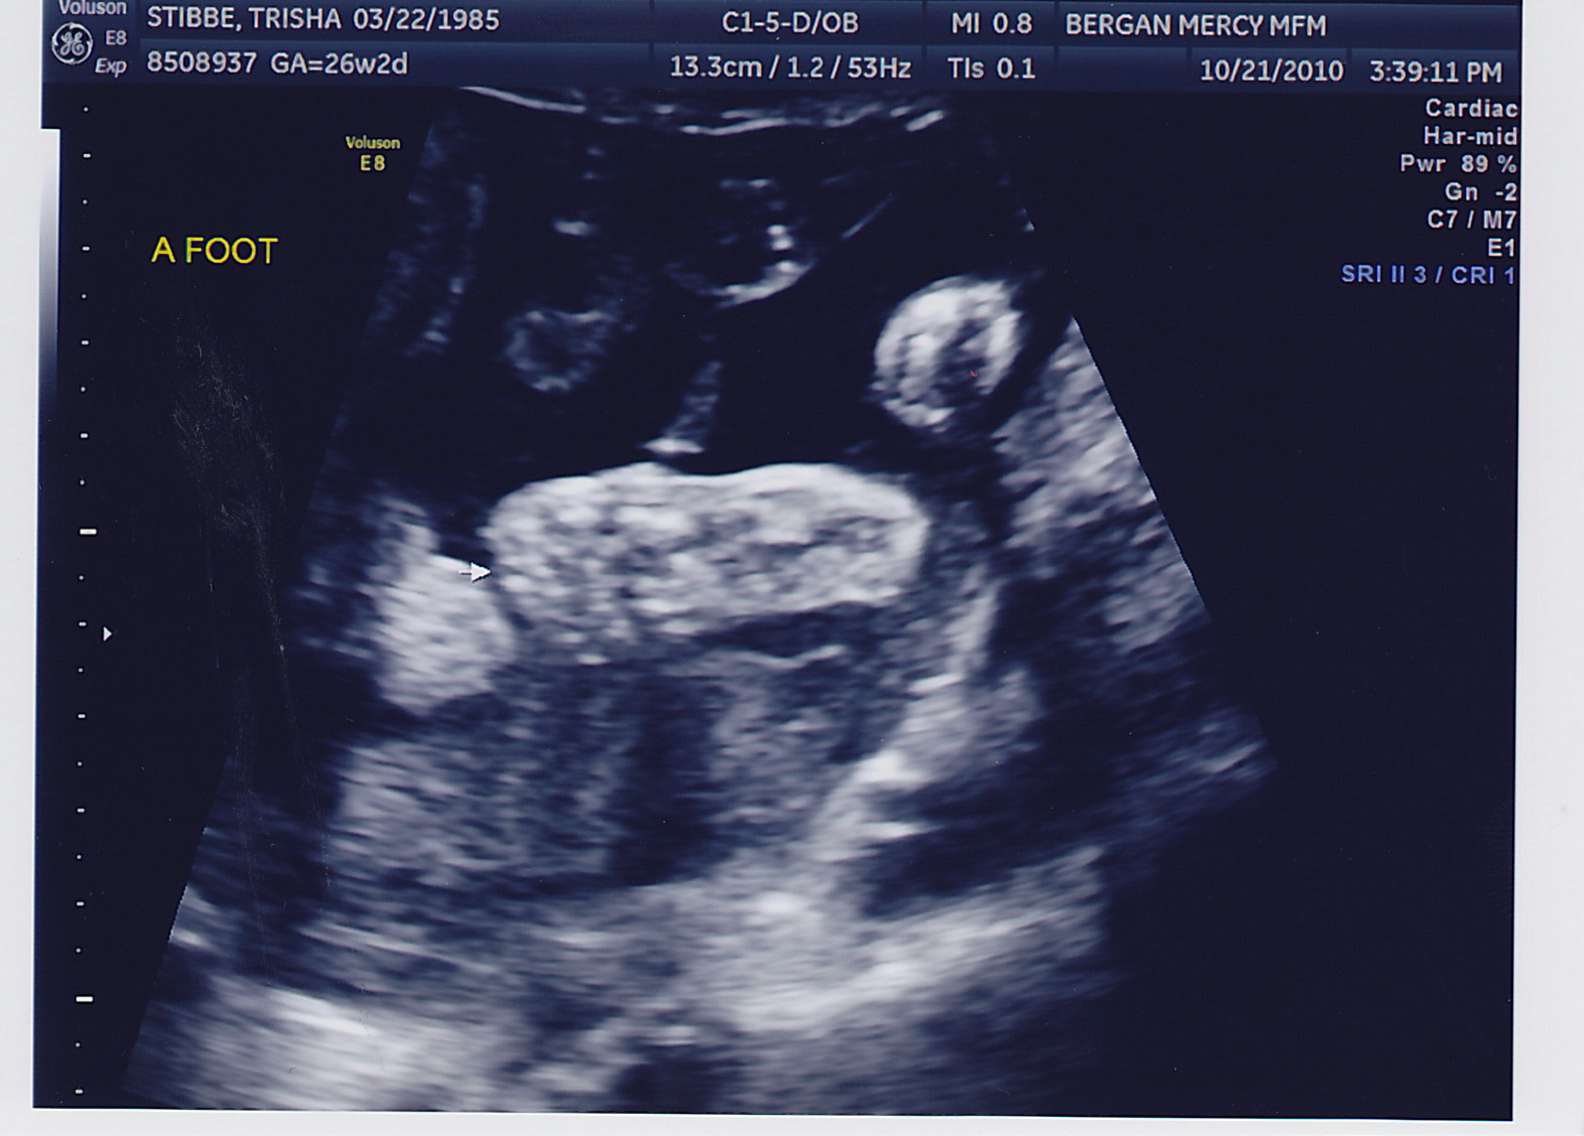

The appointment went very well. Little boys have been very active and moved around! For the past few weeks they’ve both been breech and on either side. This week Baby A’s head is just over my belly button and is kind of in a c-curve down the left side of my stomach. Baby B is head down and is kind of tucked into the curve of Baby A.

Again… they were camera shy! Only with their faces, not their “boy parts” 🙂 They sure are proud to be little boys!!

The fluid in Baby B’s brain actually decreased some, so that was great news. Also, his dopplar on the ultrasound looked pretty good. Things are on the right track… I ALMOST feel like this is a normal twin pregnancy. Almost! It’s nice to just be excited about the pregnancy and the babies now, instead of constantly worrying.